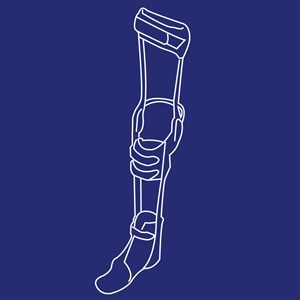

Dropfodsortose med led

Type: pdf

Størrelse: 1105 KB